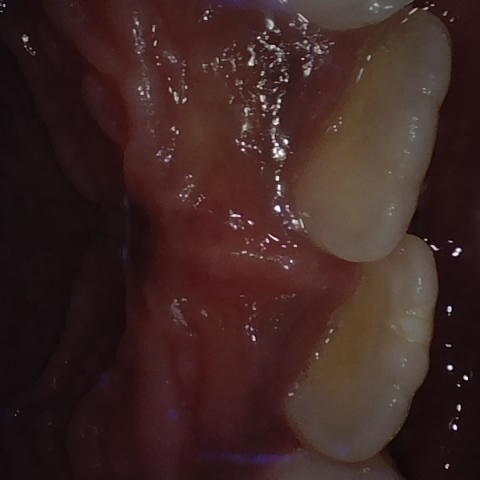

Annotated as "Good"